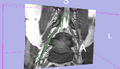

We are developing a nerve segmentation algorithm for the automatic isolation of nerves and nerve ganglia inside the spinal sack and out through the vertebrae in new MR Myelography images. Current progress can track the core of a Nerve.

Currently we use a particle-filter tracking approach for segmenting the nerves. The algorithm is given a seed point, preferably somewhere in the spine. The particles are tubes following Bézier curves (and hence forming a B-spline track). The dynamics model encourages continuity and smoothness. The image likelihood model compares gradient fields and intensities of predicted patches with image observations to evaluate a posterior distribution of the particles' importance. While we can currently usually track the nerve cores, usually fully throughout the vertebral canal, the algorithm does not delineate the full extent of the nerves and has sudden changes, and behaves poorly on peripheral nerves outside of the vertebral canal. We will modify the likelihood function and parameters and concentrate on achieving this during the project week.

• Sudden changes in the segmentation can be ameliorated. In general, can now constrain the radius function to be smoother in the general (visual) sense not just in the technical mathematical sense, to avoiding sudden changes in the segmentation (which are simply areas with fast but smooth radius function change).

• With careful characterization of the newer radius function, we can segment some of the thinner peripheral nerves. This is still specific to the images explored, but it can be done.

Results are attached: